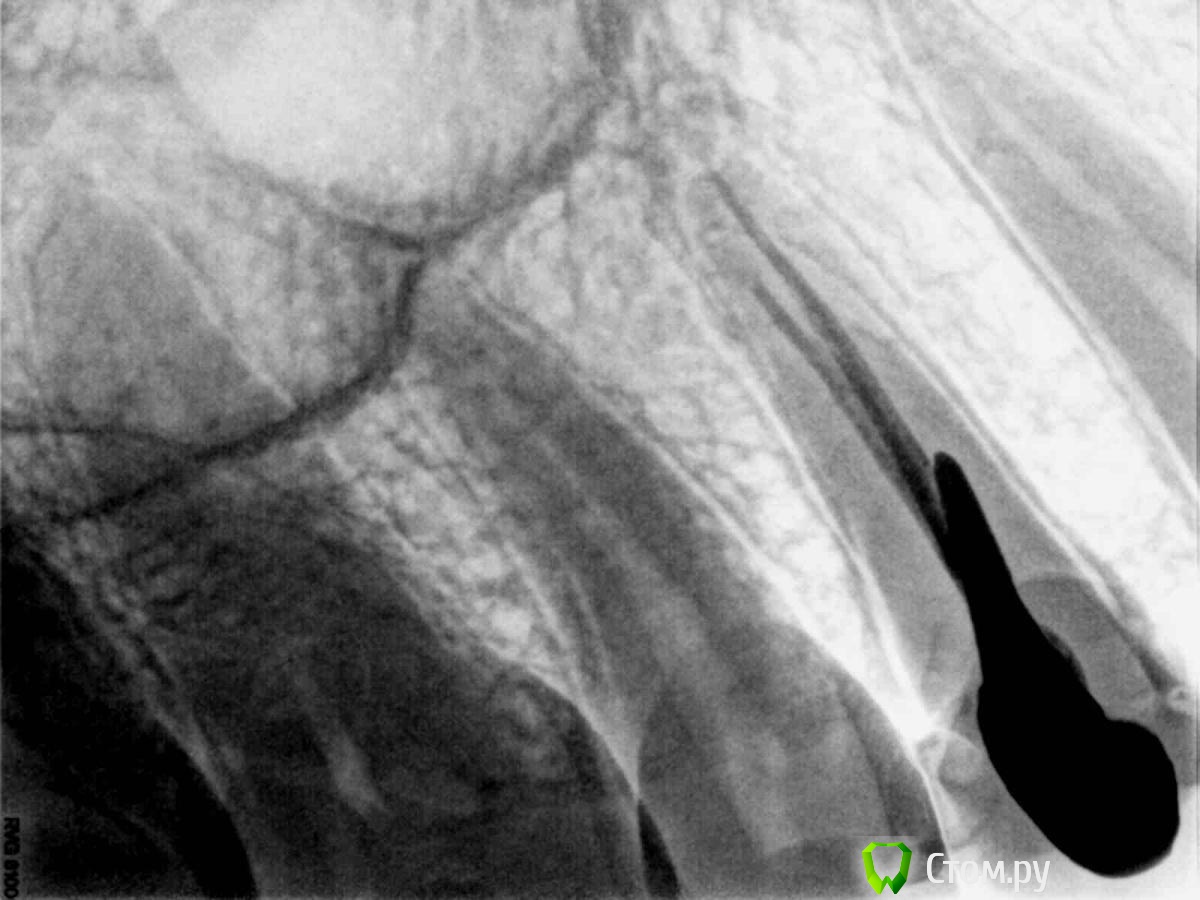

Полина83 Опубликовано 18 июня, 2014 Поделиться Опубликовано 18 июня, 2014 Здравствуйте! Помогите пожалуйста советом. На прошлой неделе мне установили металлокерамическую коронку сразу на постоянный японский цемент фуджи, имеется культевая вкладка. Не могу привыкнуть к коронке, хотя её уже подтачивали, даже слегка оголился металл. Когда я смещаю челюсть всё встаёт на свои места, но это уже не мой прикус. Челюсть стала немного болеть, ухо с этой стороны у меня сейчас тоже заболело. Возможно боль в ухе не связана с коронкой. Можно ли снять такую конструкцию без ущерба зубу и культевой вкладке?Каким инструментом должен работать при этом доктор и насколько это трудоёмко?Фото Культевой вкладки прилагаю, тоже стоит не совсем удачно Ссылка на комментарий